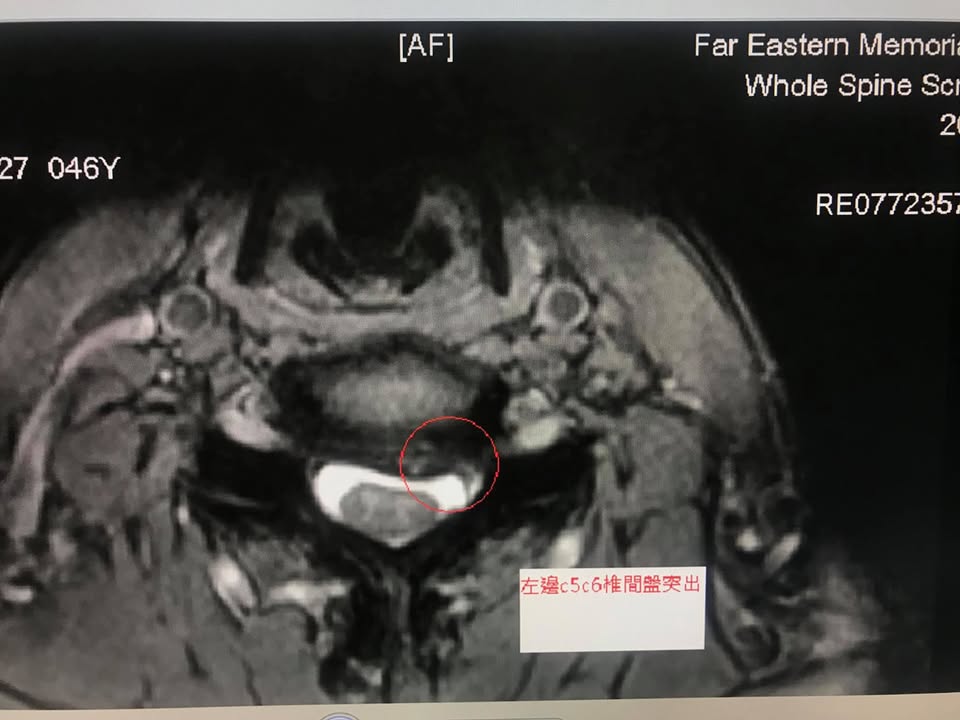

🌅這是一個很特別的案例,身為父親,大部分的爸爸習慣把寶貝小孩放在頸椎跟肩膀上面,這一個充滿父愛的動作卻造成張先生長達數年的頸椎疼痛,故事是這樣的,張爸爸從小孩零歲揹到四歲,小孩年紀小重量輕沒啥大礙,但是小孩也有十幾公斤阿,有一次在動物園看長頸鹿,因為行走的距離長一點點,他把小孩舉起來要放下來,不慎被小孩雙腳一踢,踢到頸椎,當下就聽到頸椎跟肩膀交會地方有一點異音,回家發現前胸悶痛,有點類似神經抽痛,因為懷疑悶痛跟心臟有關係就去家中附近的亞東醫院心臟科徹底檢查,索性排除心臟問題,又再過三個多月,某天騎摩托車帶全罩安全帽撞到坑洞又突然胸口悶痛跟頸椎痠痛一下,又去神經內科拍片子,發現頸椎關節有一點塌陷,一開始請患者拉脖子,拉一周後症候消失,過了半年都沒什們事情,但是很特別的是張先生原地跳躍這個動作會誘發胸口悶痛而且頸椎以經開始慢性悶痛,一直到民國107年二月開始手麻了,有一天睡覺翻身突然麻醒,無名指跟小指感覺異常,之後伴隨右手上臂會有麻痛的感覺,左邊無名指跟小指也會麻,從此之後睡覺品質大幅度下降,因為麻到醒過來的頻率很高,當年七月底神經外科安排拍攝mri(照片在下面)証實頸椎第五第六與第七都有突出現象,建議做人工椎間盤手術,張先生還是想嚐試保守治療,但是一般針灸推拿按摩做了很多次,效果當下可以,但是一直無力持久,有時候只有舒緩幾個小時而已!!